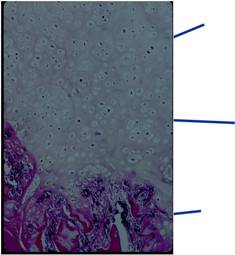

Microscopic Pathology

Pathology:

- Medullary and cortical continuity w/ underlying bone

- Hyaline Cartilage Cap with lobular growth

- Cartilage cap involutes after growth